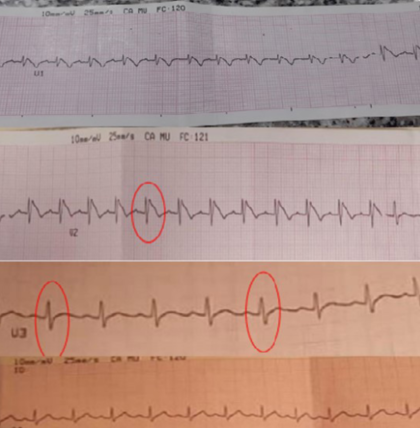

Electrocardiograma: ritmo regular, sinusal, frecuencia de 120 latidos por minuto, QRS normal. Supradesnivel de segmento ST en derivada V2 y V3 compatible con trastorno de la repolarización e injuria miocárdica a nivel septal (Figura 2).